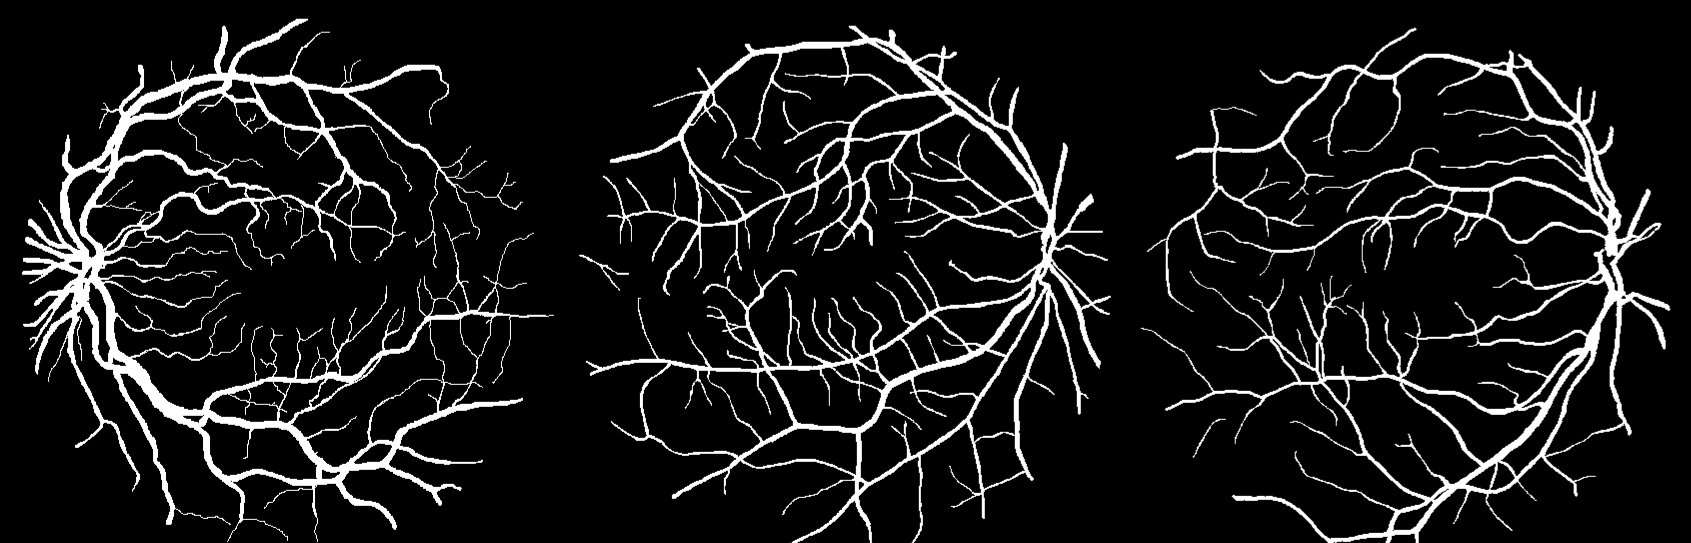

Fig. 3: Visualization of the prediction made by our proposed technique on three samples randomly taken from the DRIVE dataset: (a) Original preprocessed image (b) Corresponding ground truth and (c) Segmented output.

Fig. 3 shows the qualitative outputs of our proposed method. More visualizations of results and intermediate results can be found at project website 111https://avijit9.github.io/my_posts/FCN_Retina.html.